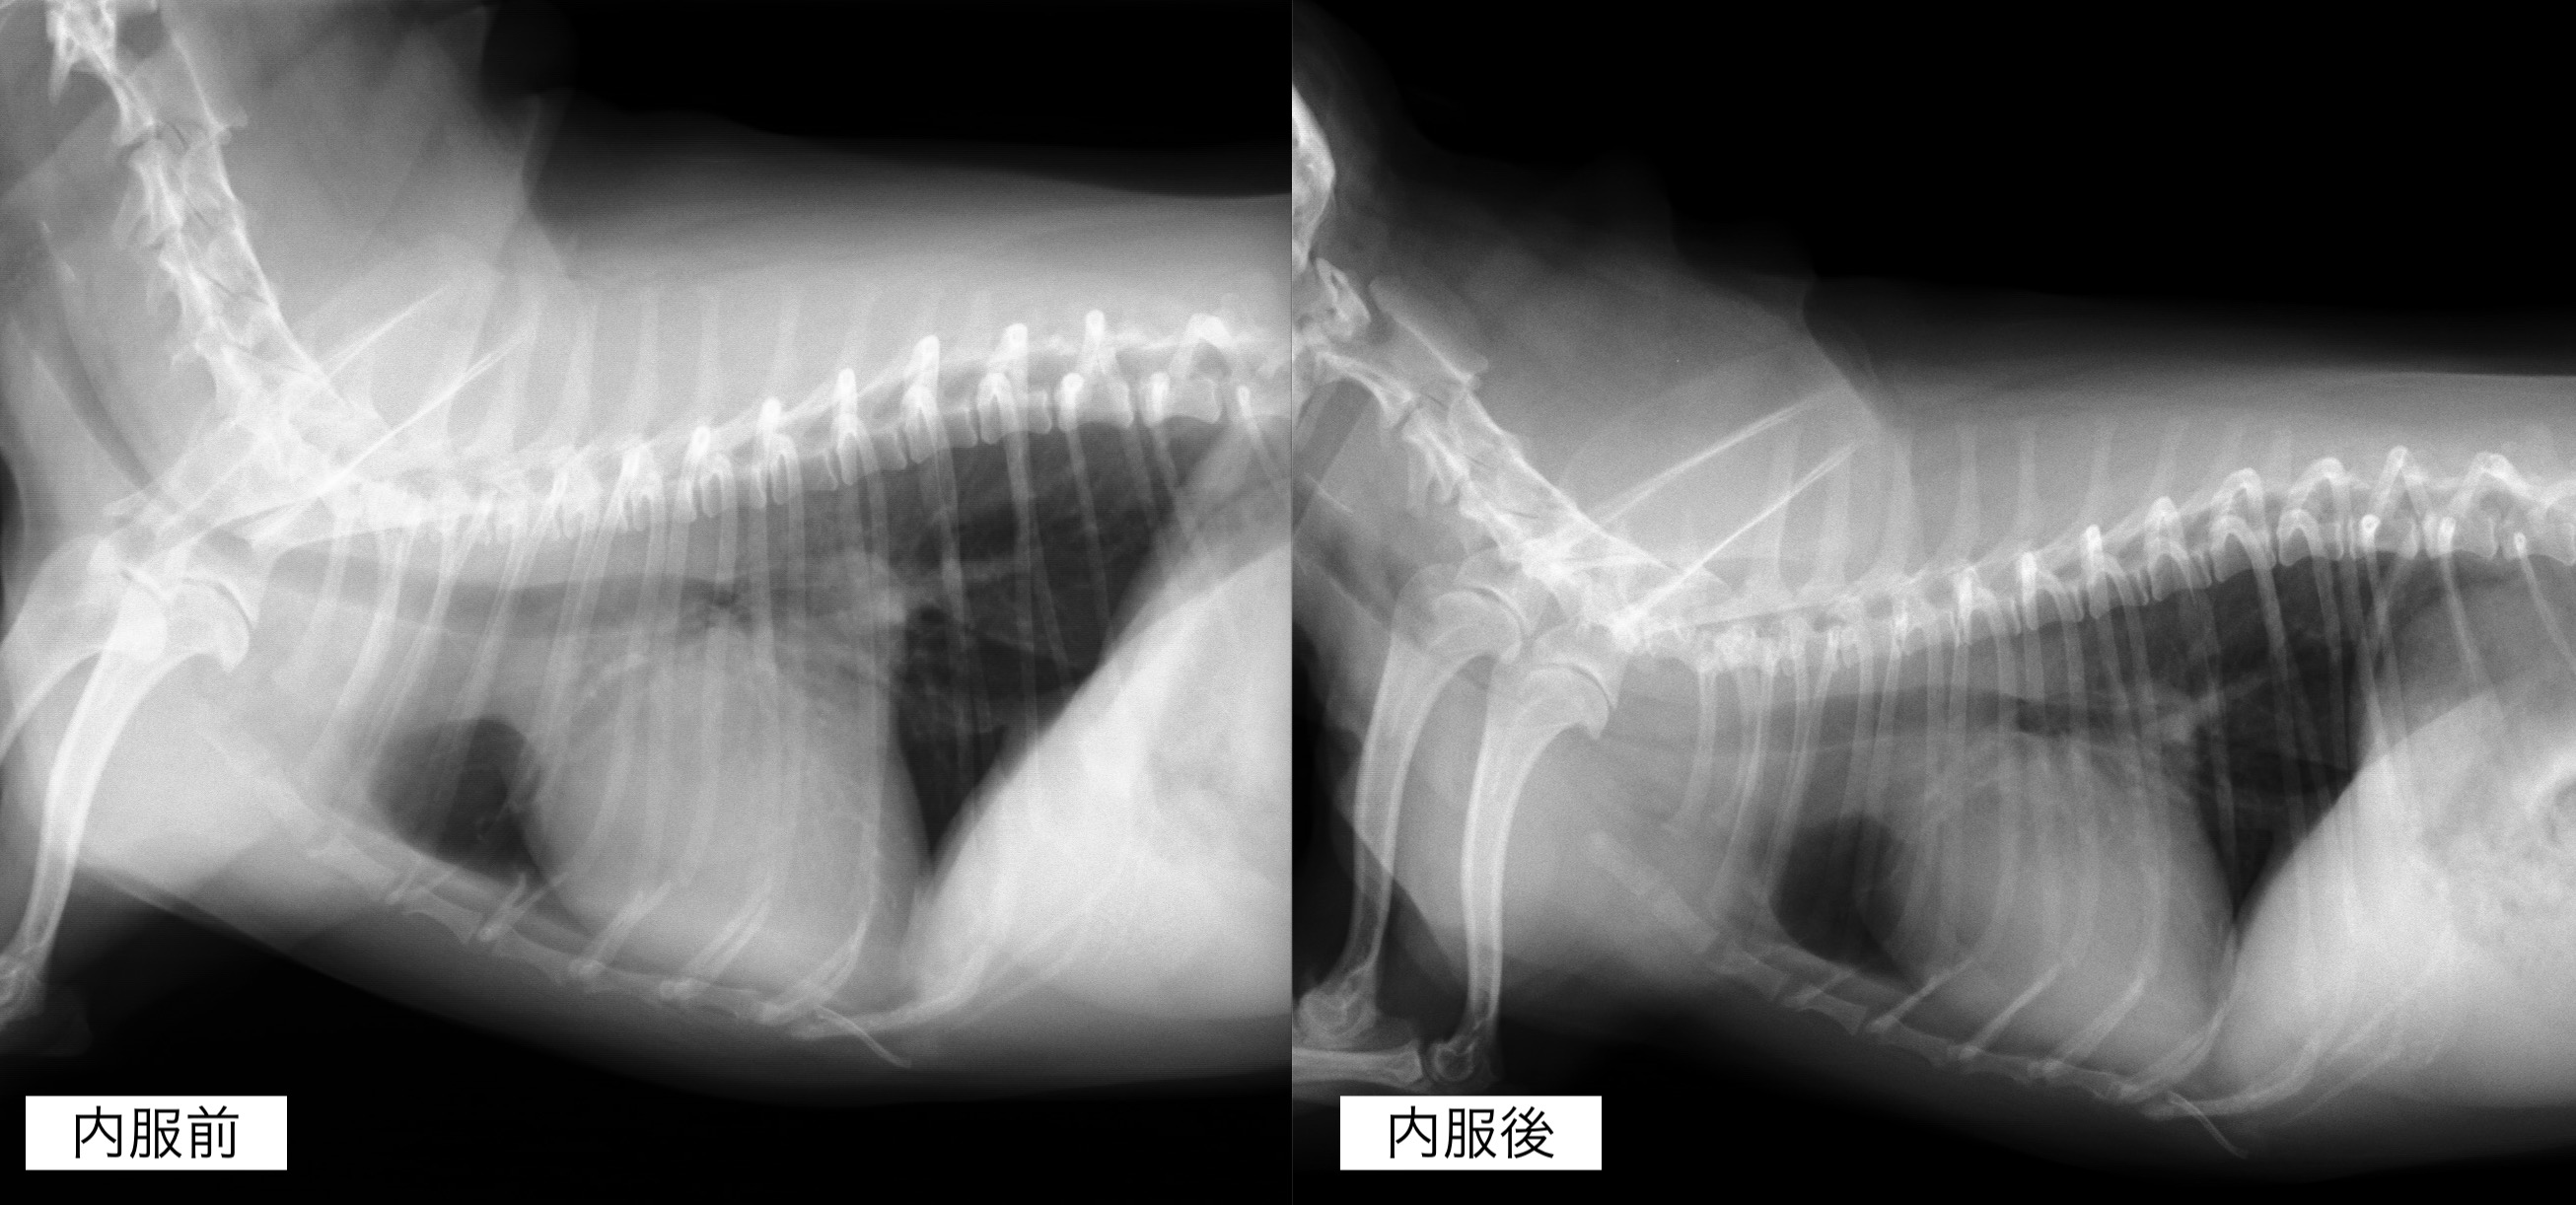

聴診検査にて心雑音が観察され、レントゲンん検査では心臓の明らかな拡大が認められました。

内服開始1ヶ月後のレントゲン検査です。

心臓の拡大はやや改善しており、咳の頻度も減っているとのことでした。